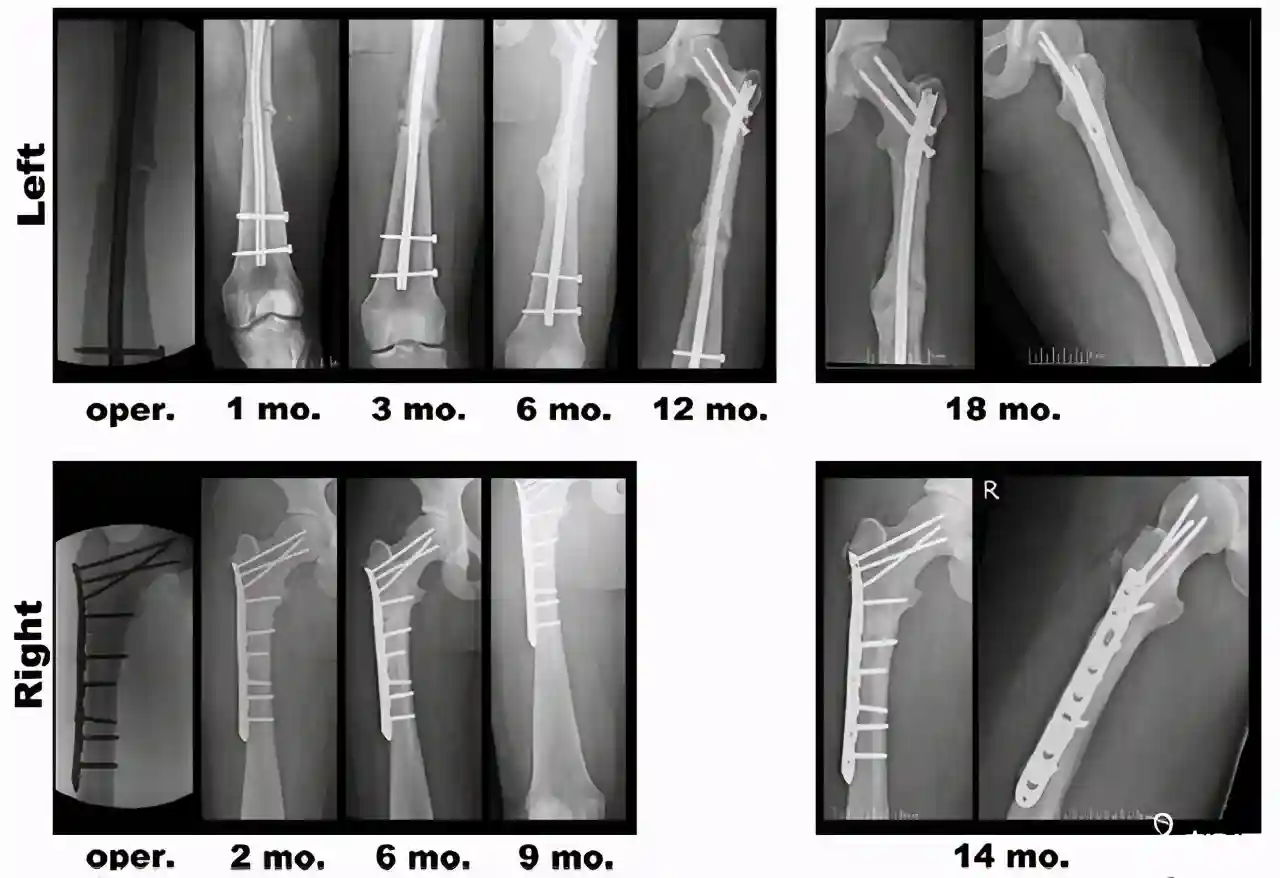

1、X线检查

根据骨不全症的患者X射线的表现有很大的不同,根据骨不全症的类型不同。一般来说,长骨基干细长,构成关节的骨端粗,骨小梁少,基干弯曲,凸侧皮质薄,凹侧比较厚,髓腔比较大,囊性发生变化。有很多既旧又新鲜的骨折线。头盖骨石灰化较晚,颅板变薄,间隙骨变多,前脑腔和乳突洞变宽,双下巴突出,头表面上下变小,形成倒三角。椎名扁平,呈双凹形,皮质变薄,骨质松弛,脊柱侧弯曲或后突起。肋骨骨折也很多。骨盆是三角形,骨盆的空洞变小。